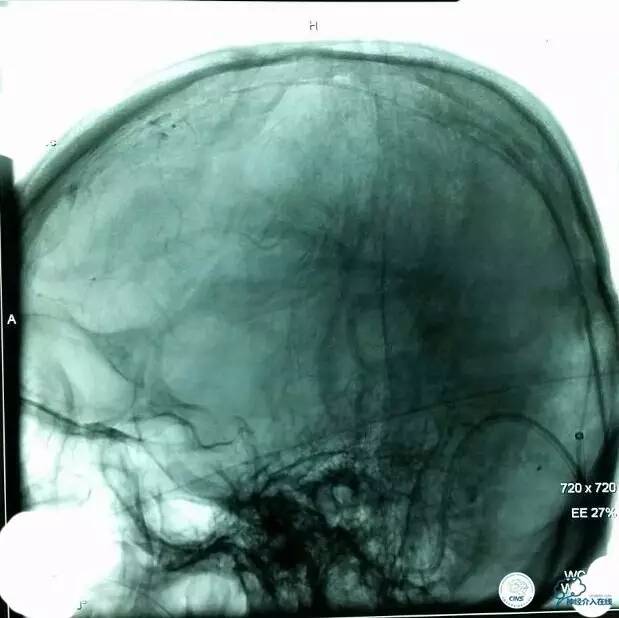

▼正位造影:

▼正位: